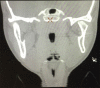

Temporomandibular joint (TMJ) ankylosis in children is one of the most complex and challenging problems managed by oral and maxillofacial surgeons. TMJ ankylosis in growing children often leads to facial deformity, difficulty in chewing and swallowing, severe malocclusion, poor oral hygiene, multiple decayed teeth, and impairment of speech. A good functional and esthetic outcome can be achieved after reconstruction with the autogenous grafts. Here, we present a case of a 9-year-old patient treated with condylectomy and ipsilateral coronoidectomy, followed by reconstruction with costochondral graft with 5 years of follow-up. During this period, the reconstructed graft remodeled into a neocondyle and also regrowth of the coronoid process. The mouth opening and facial symmetry were acceptable.